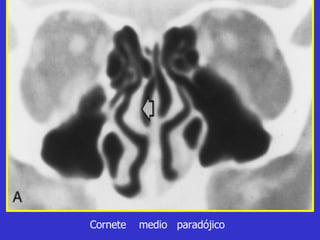

Este documento describe las diferentes proyecciones radiográficas utilizadas para examinar los senos paranasales, incluyendo las proyecciones básicas de Caldwell, Waters lateral y las proyecciones especiales como Hirtz y Waters mentonasal. También describe las diferentes estructuras anatómicas que componen el complejo ostiomeatal anterior y posterior de los senos paranasales.